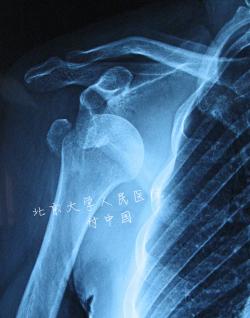

肩关节脱位伴大结节骨折